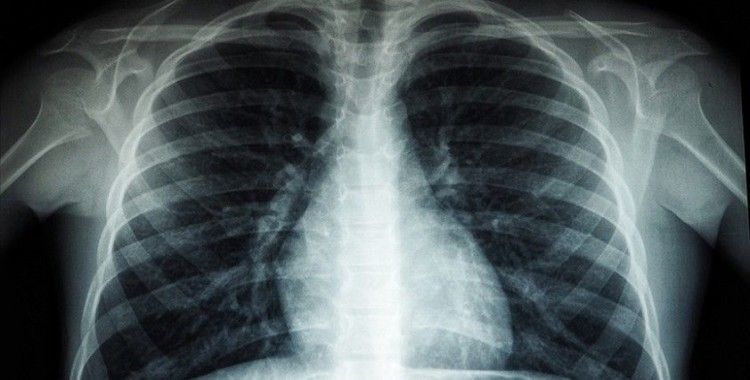

Araştırmacılar, ağır Kovid-19 hastalarında akciğerlerde kan pıhtıları oluşması nedeniyle, Heparin’in kan sulandırıcı etkisinin bu tür pıhtıların oluşumunu engelleyebileceğini aktardı.